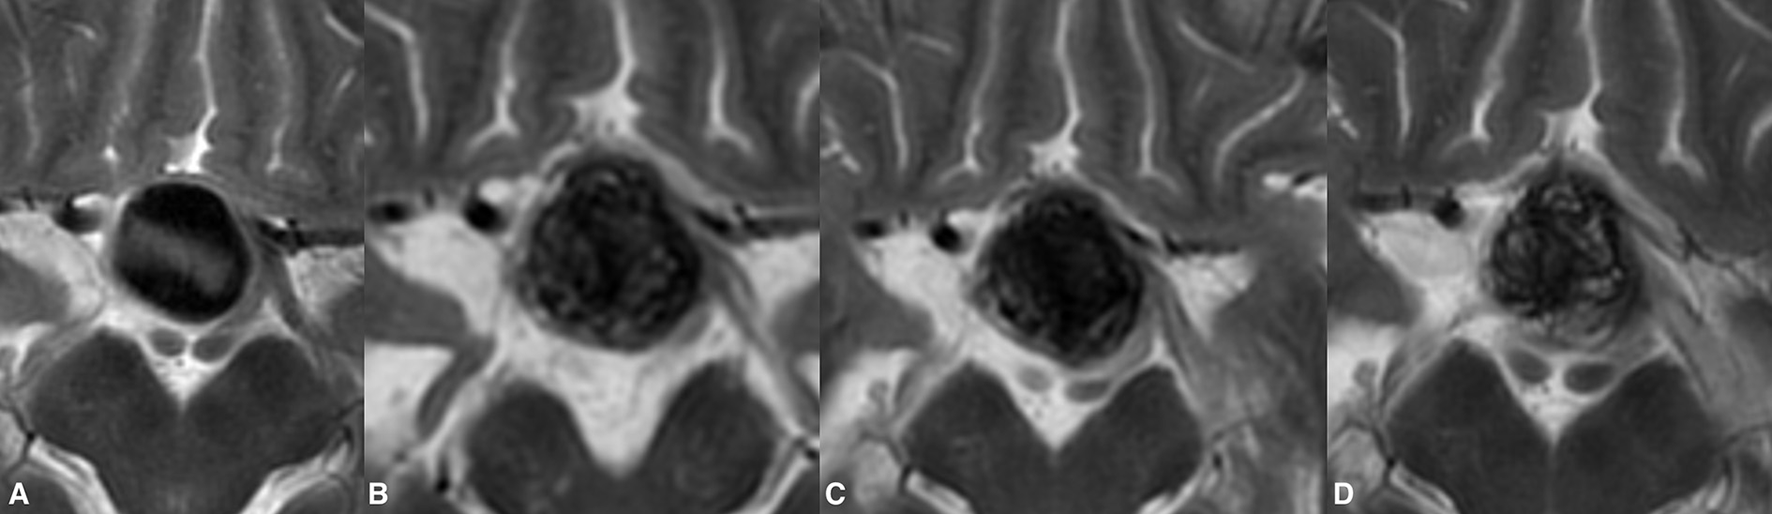

Figure 2

Post-treatment enlargement of a giant paraophthalmic ICA aneurysm (A). During routine clinical examinations, the patient showed temporary aggravation of the presenting visual symptoms due to increase chiasmal compression. The first radiological follow-up demonstrated the treatment-related volume increase of the treated aneurysm (B). Following prolonged steroid and NSID therapy, the patient's visual status improved notably. Twelve months after the treatment, the observed growth of the aneurysm was seized with documented aneurysmal shrinkage (C). Lack of signal void within the aneurysm on T2WI in the same patient at 24 months indicates the ongoing aneurysm thrombosis (D). The last follow-up also noted the collapse of the previous growing aneurysm.